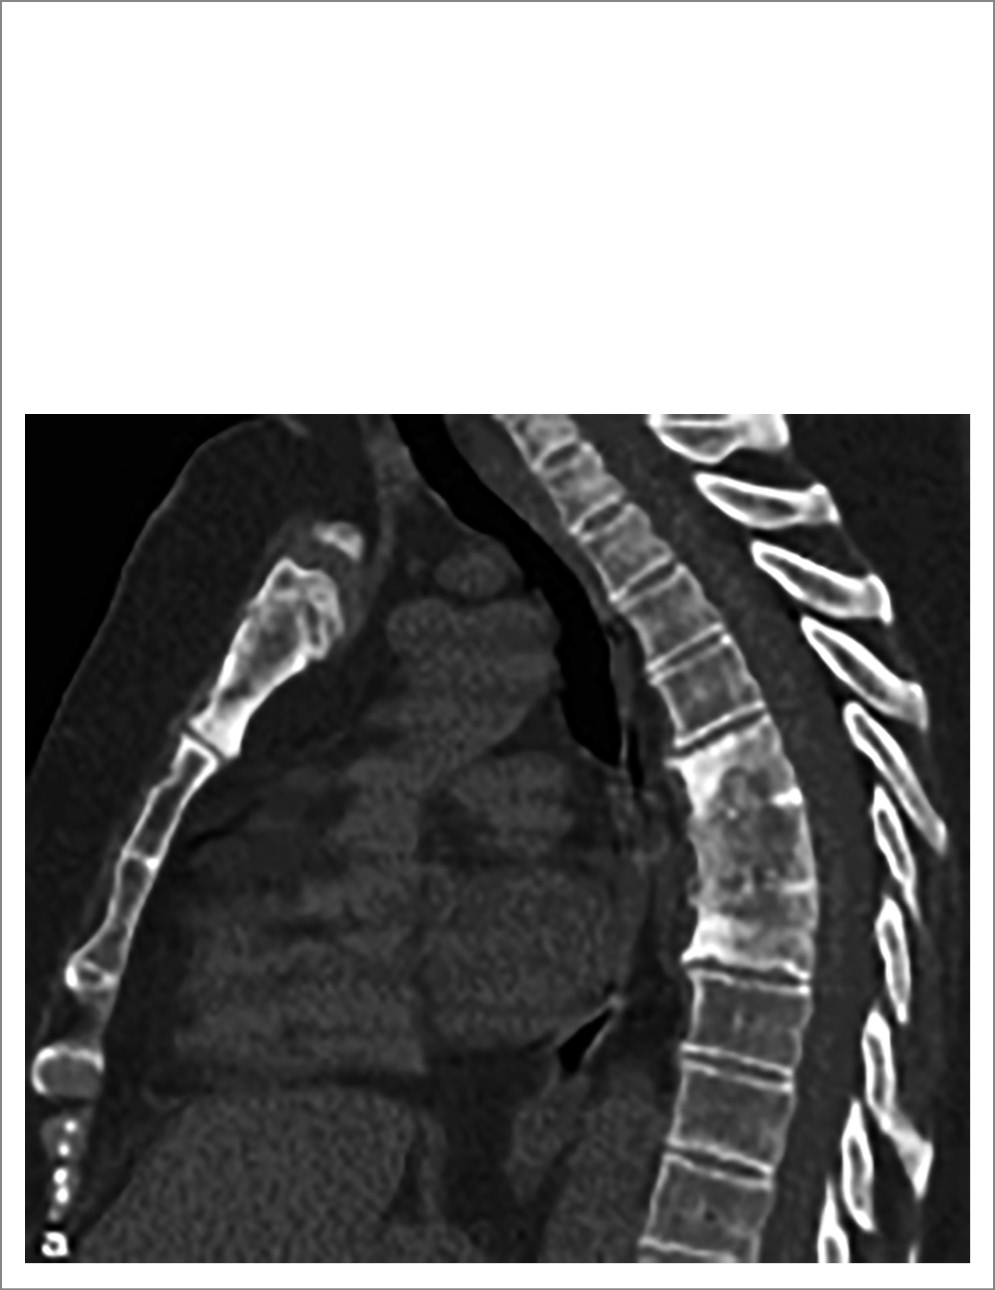

Синдром SAPHO – остеоартропатия, характеризующаяся поражением ключиц и грудины, суставов между ними и передних отрезков 2 верхних ребер с развитием деструкции и (что особенно своеобразно) избыточного костеобразования (гиперостоза). Синдром SAPHO считается одной из клинических форм хронического небактериального остеомиелита – аутовоспалительной болезни костей. Другими формами данного заболевания являются изолированный диффузный склерозирующий мультифокальный остеомиелит и хронический рецидивирующий мультифокальный остеомиелит. Последнее заболевание начинается в детском или подростковом возрасте, отличается избирательным поражением метафизов трубчатых костей нижних конечностей, но может также приводить к поражению позвоночника и КПС, сохраняющемуся у взрослых. Основу патологии при синдроме SAPHO составляет остеит, вызывающий костно-суставную деструкцию и последующее чрезмерное костеобразование в местах поражения скелета. У 30–50% пациентов отмечаются очаговые или сегментарные («разбросанные») изменения позвоночника, малосимптомные или клинически яркие, проявляющиеся болями и ограничениями движений (рис. 7). Возможен и сакроилиит. На МРТ может быть найден отек КМ в телах позвонков (в одном или нескольких), нередко значительный по площади и иногда дискообразный по форме, примыкающий к замыкательным костным пластинкам и сопровождающийся их повреждением. Указанные изменения напоминают спондилодисцит, хотя межпозвонковые диски поражаются редко. Патологический процесс не распространяется на оболочки спинного мозга и околосуставные мягкие ткани (в отличие от инфекционного спондилодисцита). Со временем в пораженных сегментах позвоночника может развиваться параспинальная оссификация в виде недисковых синдесмофитов или спондилофитов. Остеоартропатия при синдроме SAPHO часто сочетается с шаровидными акне или гидроаденитом, а также с ладонно-подошвенным пустулезом, выявление которых способствует правильному диагнозу. Частота лейкоцитарного антигена гистосовместимости B27 (HLA-B27) не повышена [18, 19].

Рис. 7. Пациентка П., 55 лет. Диагноз – синдром SAPHO (длительность – 10 лет) с поражением грудины, ключиц, грудного и поясничного отделов позвоночника; пустулез ладоней и стоп. Проведена КТ органов грудной клетки (сагиттальная плоскость): видны клиновидная деформация тел ThVI,VII,VIII, их анкилозирование, очаги деструкции и склероза, эрозирование нижней замыкательной пластинки ThVIII, передние остеофиты. Имеется также остеит рукоятки грудины: расширение контуров (гиперостоз), очаги деструкции и остеосклероза.